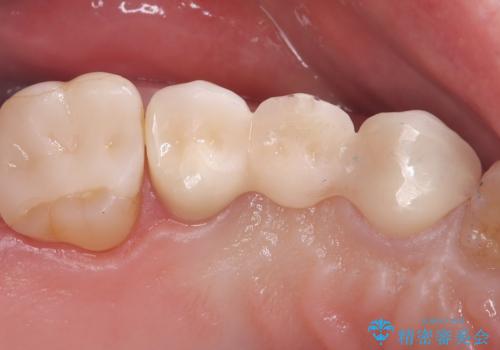

【セラミッククラウン】歯が欠けた!

- 主訴:ブリッジの歯が一部欠けた

右上⑤4③でメタルフレームを用いたブリッジが既に入っており、その内右上5番目の歯がう蝕により欠けてしまっていました。

元々5番目の歯には4/5冠が入っていましたが、ブリッジのやり替えに際しクラウンとしました。

右上5はう蝕除去後は間接覆髄を行いCR裏層しています。う蝕が大きく神経症状が出ないか経過を確認しクラウンの印象を行っています。